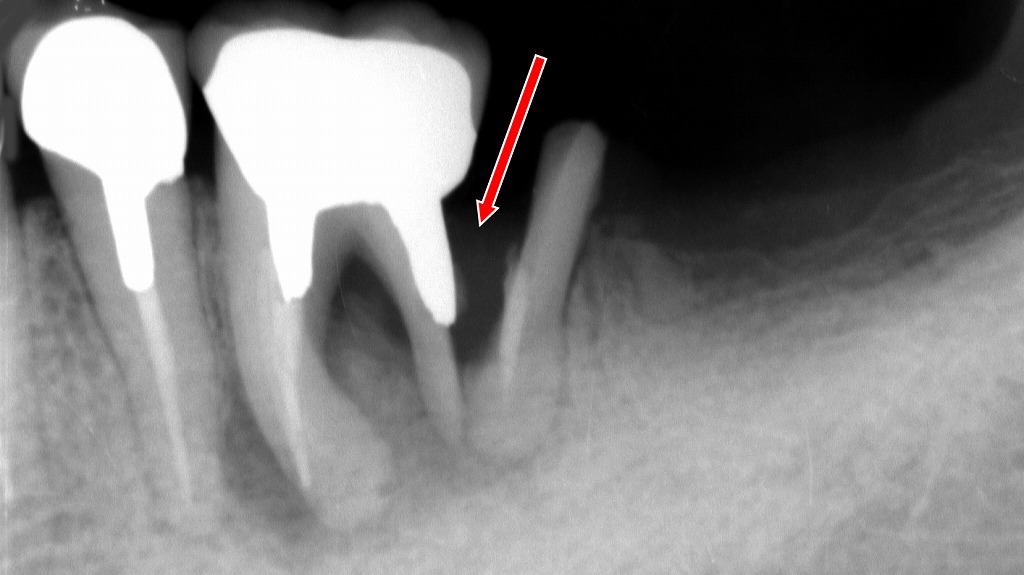

- 3.3.1. 上下大臼歯における精密な根管治療の良好な根管充填例

上下大臼歯における精密な根管治療の良好な根管充填例

下顎6番の根管形態に合わせて緊密に封鎖された精密な根管治療

下顎6番

根尖付近まで充填材が均一に到達し、複雑な根管の湾曲にも正確に追従した理想的な根管充填状態。根管内の細部まで適切に清掃・消毒・封鎖が行われており、治療後の良好な予後が期待できる所見です。